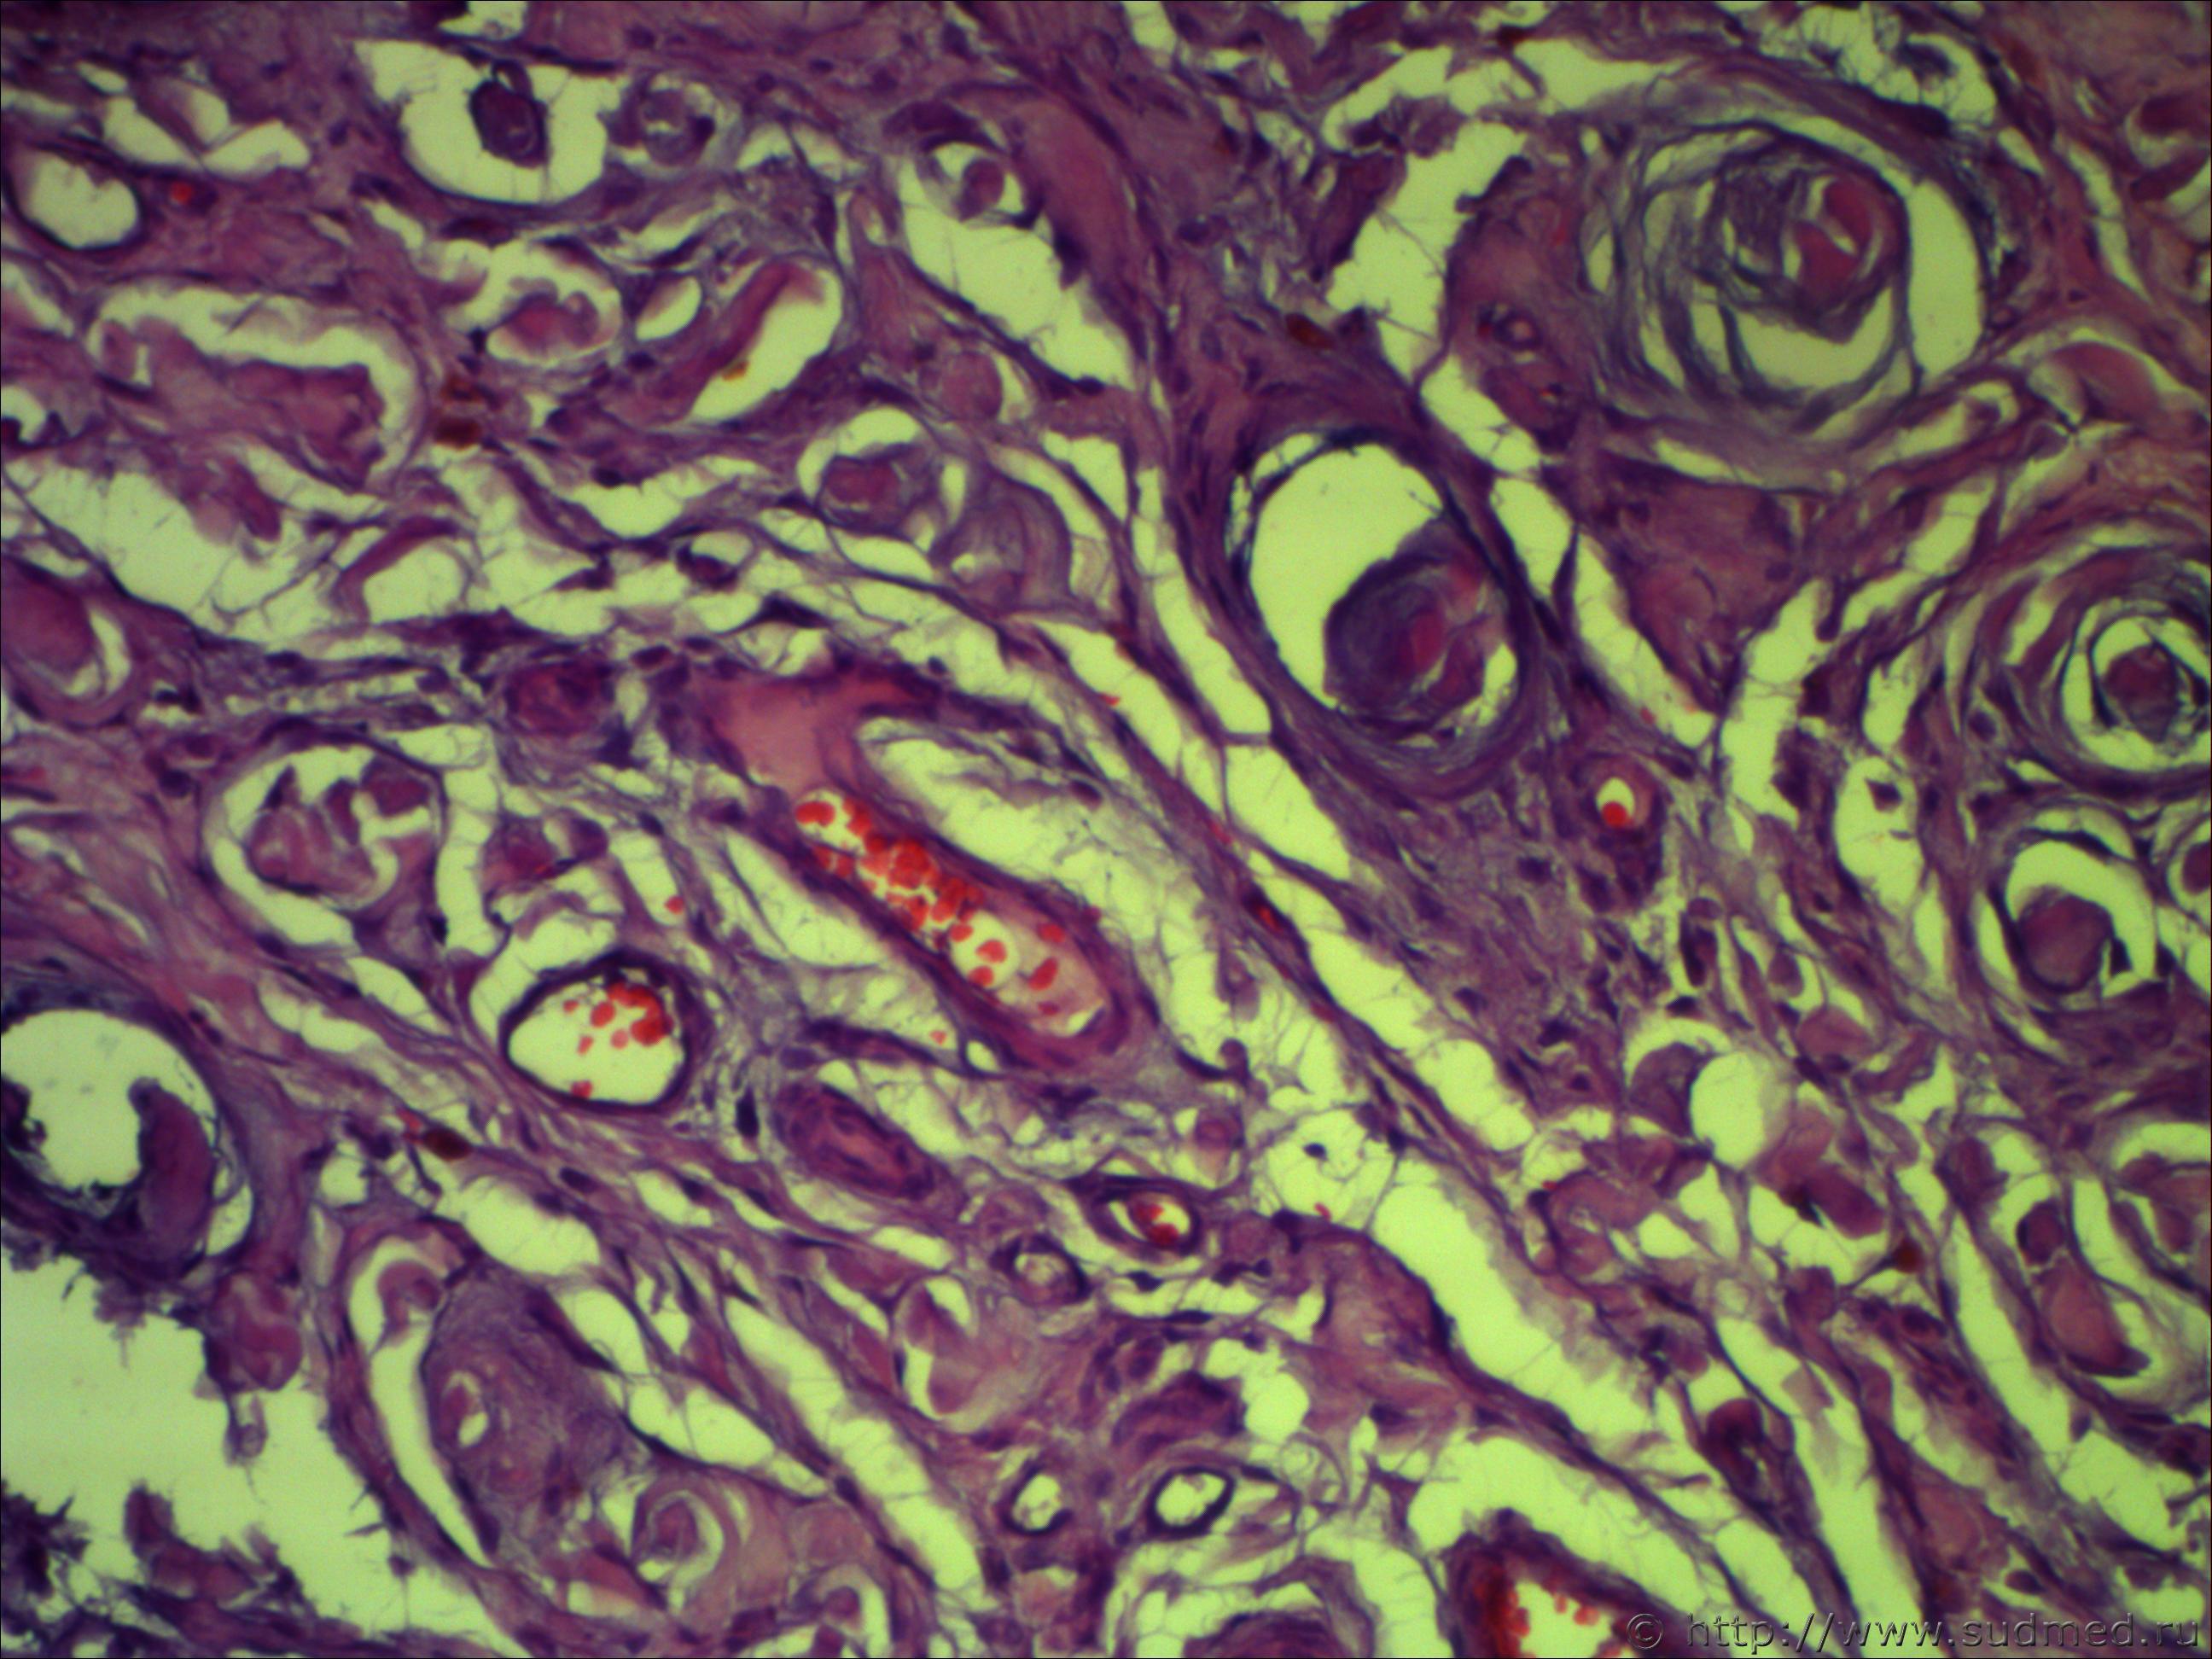

Н/О округлой формы четких границ, на теле фибринозно-кистозной структуру 5*7см!

Похоже на ангиофиброму.

Не фибринозно, а фиброзно-кистозная структура. Пока об ангиофиброматозе нужно думать, требует дальнейшей дифференциации.Срезы толстые. Наблюдается эндотелиальная пролиферация...

Ничего такого не понял, вижу:

- новообразование сосудов. полнокровие очаговое

- очаговый гиалиноз

- смешанную фиброму (типическую)... да их столько с примесью кистозного элемента

- митозов не вижу